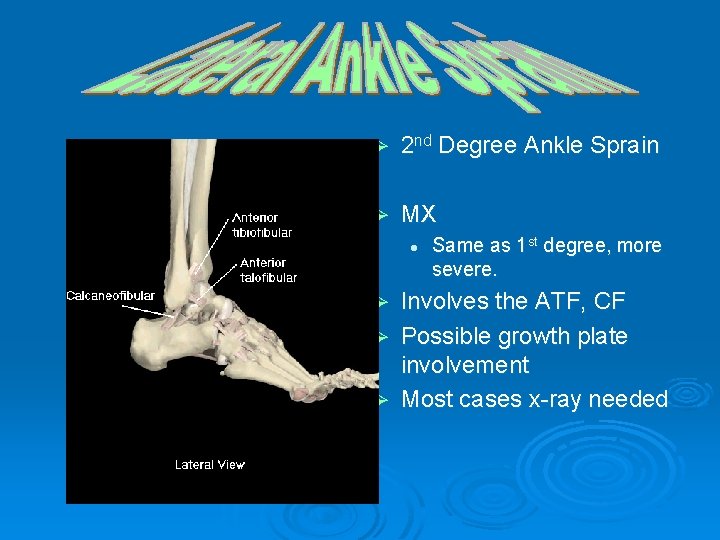

Ø 2 nd Degree Ankle Sprain Ø MX l Ø Ø Ø Same as 1 st degree, more severe. Involves the ATF, CF Possible growth plate involvement Most cases x-ray needed